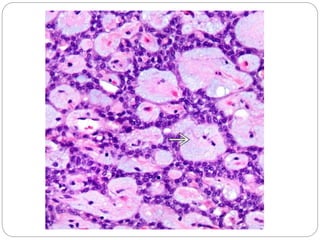

• #13 Solid sheets of tumor cells become dyscohesive and result in a characteristic pseudopapillary appearance with a central fibrovascular-like core surrounded by neoplastic cells.

• #14 The delicate vessels can have myxoid stroma or may be hyalinized.

• #16 The sheets of tumor cells have overlapping, round to oval nuclei that are oriented away from the vessels with a rim of cytoplasm toward the capillary.

• #17 Tumor cells have round to oval nuclei and sometimes exhibit longitudinal nuclear grooves . These intra- and extracytoplasmic eosinophilic hyaline globules stain positive for PASD and α-1-antitrypsin.